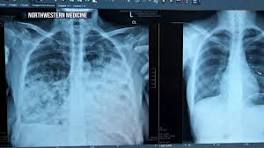

Troubling rise in young women getting lung cancer - NBC News Doctors from around the country say they are seeing more cases of young women with no history of smoking being diagnosed with lung cancer.

| She never smoked, then a CT scan found cancer in both lungs. Now she champions early ... Colette Smith of the Bronx was diagnosed with lung cancer, despite never smoking. Her survival story is central to her push for early detection.